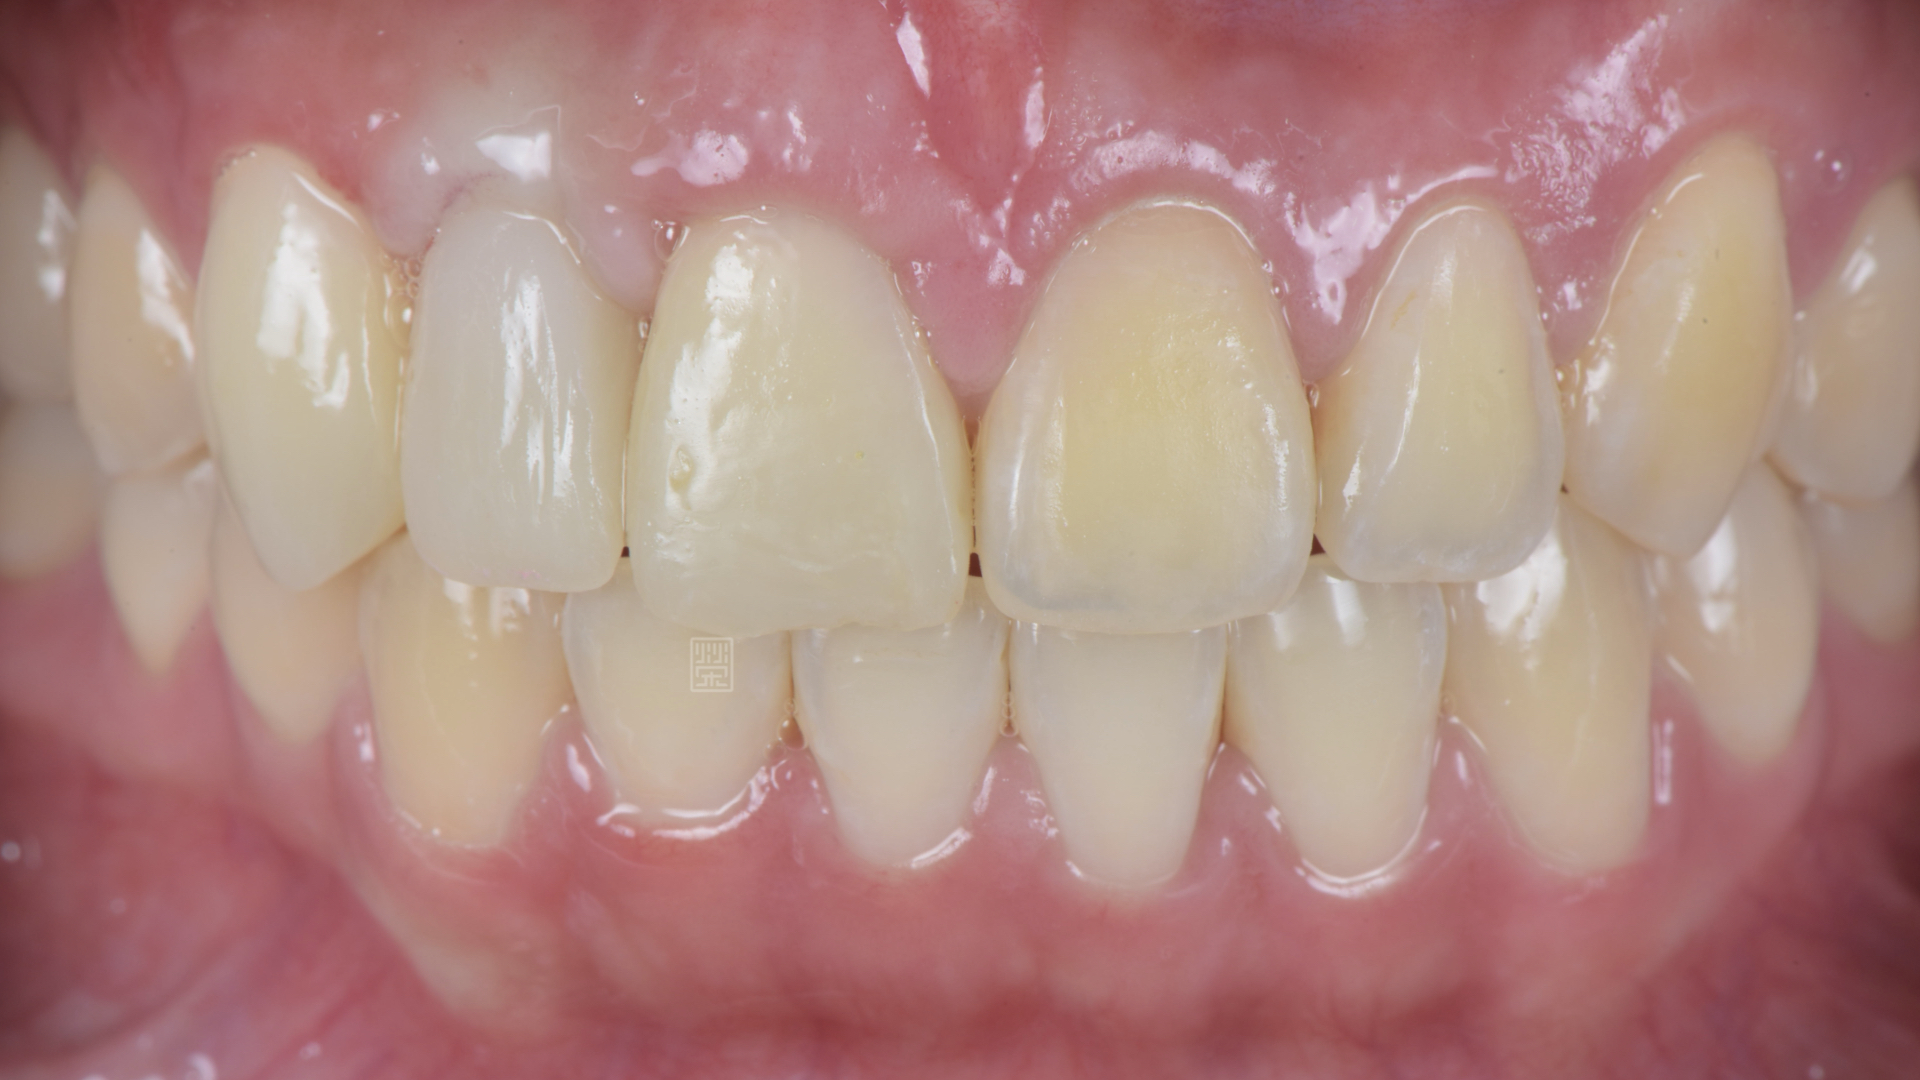

全瓷冠、植牙全瓷冠完成